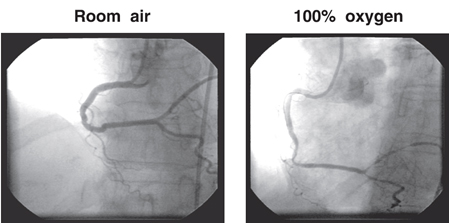

Finally the thing we have been doing so good on over the last years…Acute MI. Lets take a look at McNulty PH, et al. (Effects of supplemental oxygen administration on coronary blood flow in patients undergoing cardiac catheterization. Am J Physiol Heart Circ Physiol. 2005; 288: H1057-H1062). They demonstrated that within 5 minutes of 100% NRB coronary resistance increased 40% and coronary blood flow dropped 30%. Want to see it…

and the flow in the coronary artery…